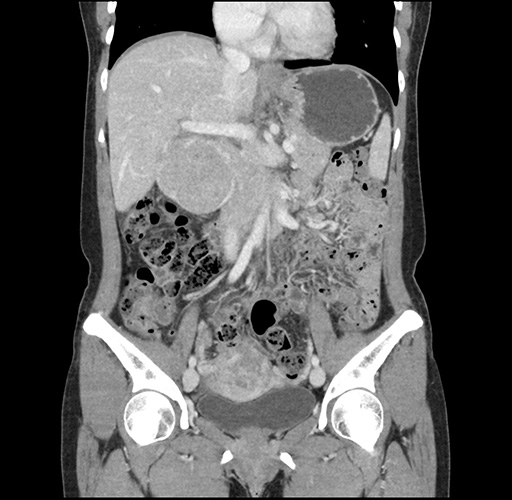

Left lateral sectionectomy [case 12]

Imaging Analysis

Look through the patient's CT scan to identify any areas of concern for the necessary procedure.

Based on your CT findings, which issue(s) would give reason for "planned slowing down moment(s)" in this case?

Considering a standard left lateral sectionectomy procedure, what step(s) of the operation would you do differently in this case ?